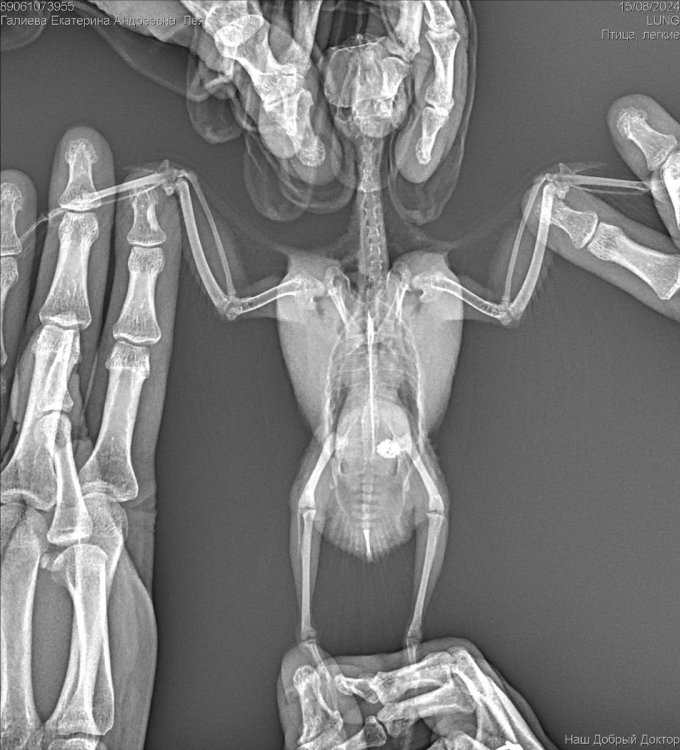

Рекомендован был рентген, по рентгену орнитолог сказала , что к попугая :

Аэросаккулит(воспаление

воздушных мешков), пневмония, нефрит, гепатомегалия, повышенная плотность костей связана с гиперестрогенизмом

Если здесь есть орнитологи, прошу помогите пожалуйста, я была на консультации 3 врачей, я боюсь давать своей птичке Амоксиклав и тербинафин целый месяц. Не много ли это ? Как вы считаете ? И пожалуйста посмотрите рентген умоляю, скажи , что вы видите ? Насколько плохой анализ помета ? И насколько серьезны поставленные диагнозы? И возможно ли это вылечить?  Остальные анализы как придут, я приложу фотографии.